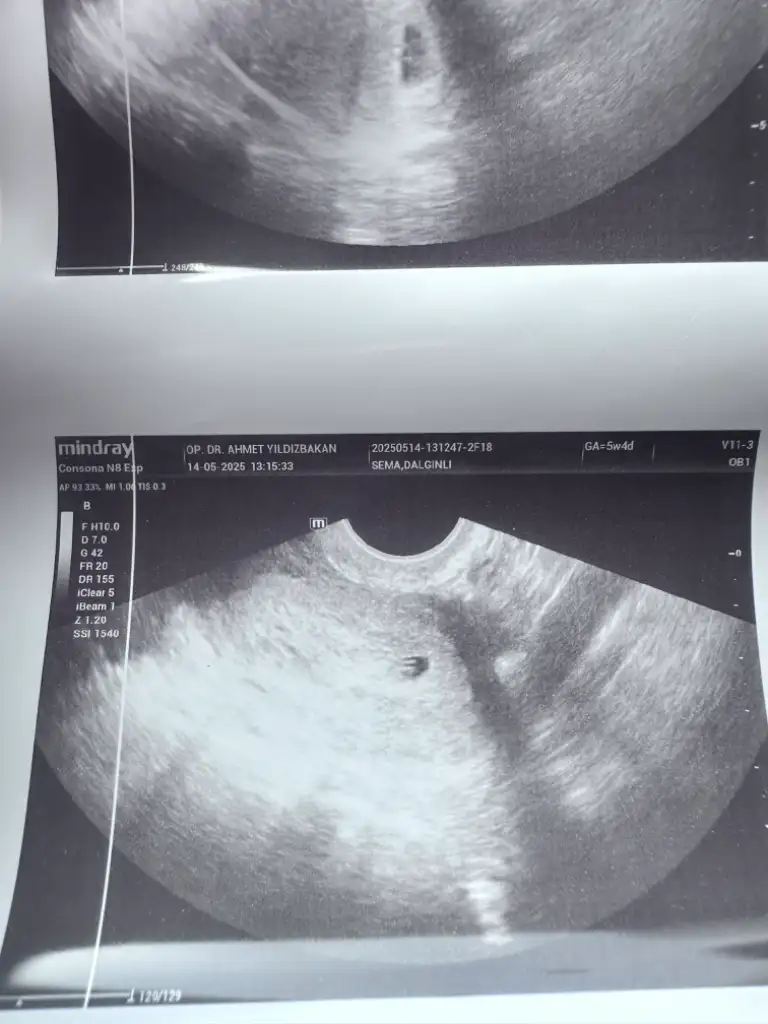

Benimkinede alttan baktı ama kaç haftalık olduğu yazmıyor ultrasyon kâğıdında ama seninkinde bebiş gözüküyor tektas gibi duruyor hayırlısı olsun bakalım 😇

5+4 haftalıksın cnm ultrasyon kâğıdın öyle dior

Sağol canım kesenin görüntüsü normal mi doktor dedi bebek oluşmuş 10 gün sonra kalp atışı için çağırdı